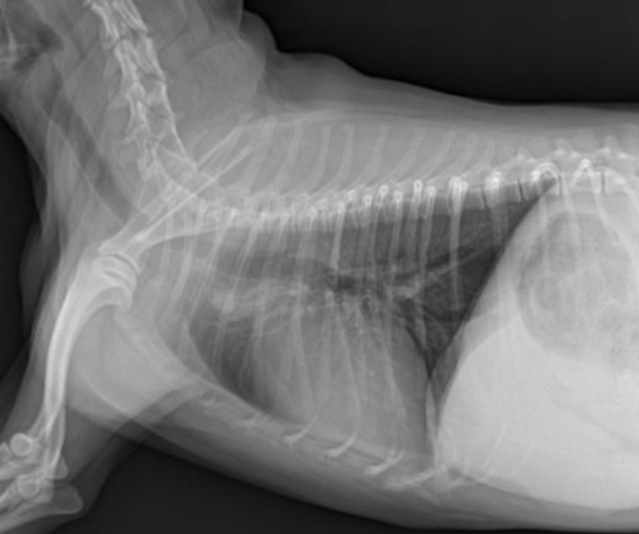

| RL (Right Lateral) | LL (Left Lateral) |

![]() | ![]() |

| ๋ ovalํจ. | ์ฌ์ฅ์ด ๋ ๋ฅ๊ธ๊ฒ ๋ณด์(round). |

| ๋ํ ์ผํ ์ฌ์ฅ ๊ด์ฐฐ์ ์ข์. | ํํ๊ด ์ดฌ์์ ์ข์. |